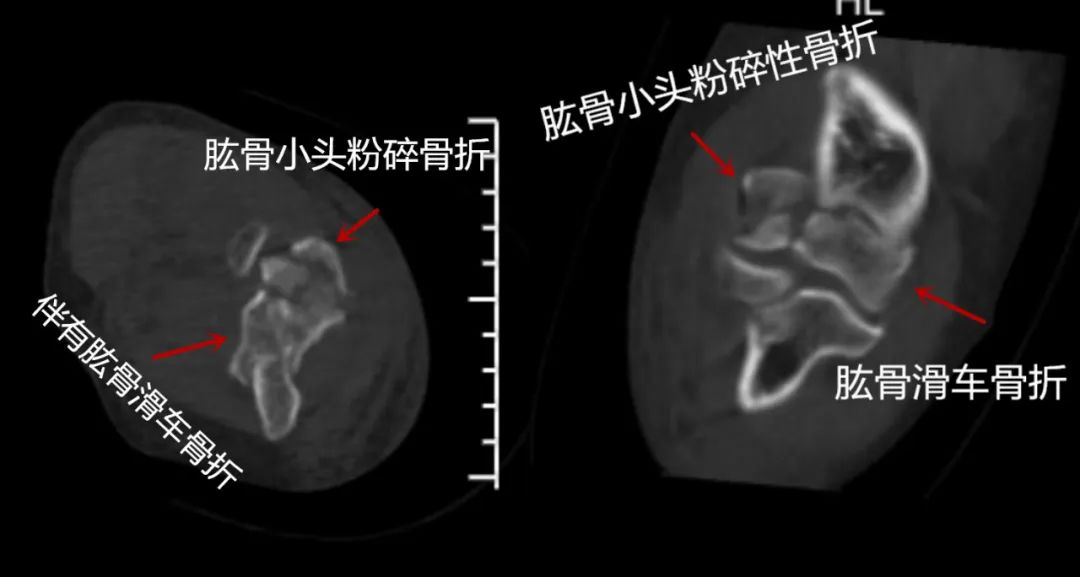

III型:肱骨小头和滑车粉碎骨折。

肱骨小头累及滑车的粉碎性骨折定义为 3 型

每亚型又根据是否累及后柱分为A、B两型。Dubberley分型综合考虑了肱骨小头前后柱的骨折情况

此外,X线上软骨不显影,实际骨折块要大于X线片显示。所以当可能是此类骨折时,应进行CT平扫加三维重建检查。